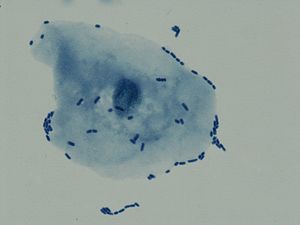

- 요 현미경 검사: 소변 침전물을 현미경으로 관찰하여 적혈구, 백혈구, 세균의 존재를 확인한다.[50] 일반적으로 백혈구가 다수(시야당 100개 이상) 관찰되고 세균이 확인되면 요로감염증을 의심할 수 있다.